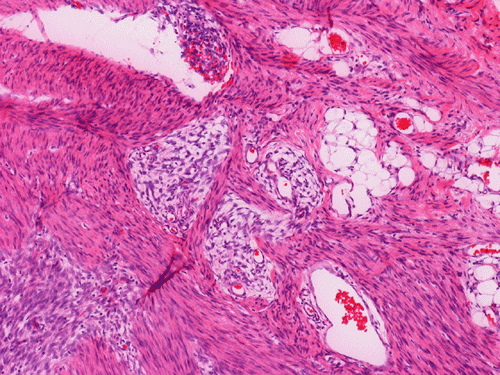

The excised mass is composed of an intermingled arrangement of mature adipose tissue, densely packed primitive spindle cells with small amount of cytoplasm, and mature appearing spindle cells with substantial amount of cytoplasm that gives the appearance of smooth muscle (Panel  A). Abrupt transition between the three elements are common (Panel B). The densely packed, small primitive spindle cells have elongated, cigar-shaped nuclei with amphophilic cytoplasm. Pleomorphism and mitotic figures are not seen. A small number of lymphocytes are present among these cells (Panel C). In areas with appeance of smooth muscle, the cells have elongated, sometime wavy nuclei without significant pleomorphism or mitosis (Panel D). Areas with thick, wavy collagen fibers admixed with benign appearing spindle cells are also present (Panel E and F) and some of these areas are more loosely packed than the other areas which may mimic the appearance of a neurofibroma. In contrast to other areas, these collagenous areas merge imperceptibly with the more cellular areas. In some of the densely packed spindle cell areas, there are small packets of loosely packed cells that give a myxomatous morphology on high magnification (Panel G and H).

On immunohistochemistry, the mature adipose cells are positive for S100 protein. The areas that morphologically suggestive of smooth muscle are positive for smooth muscle actin but the densely packed spindle cell areas are only faintly positive for smooth muscle actin. All components are negative for muscle specific actin and CD34 on immunohistochemistry.